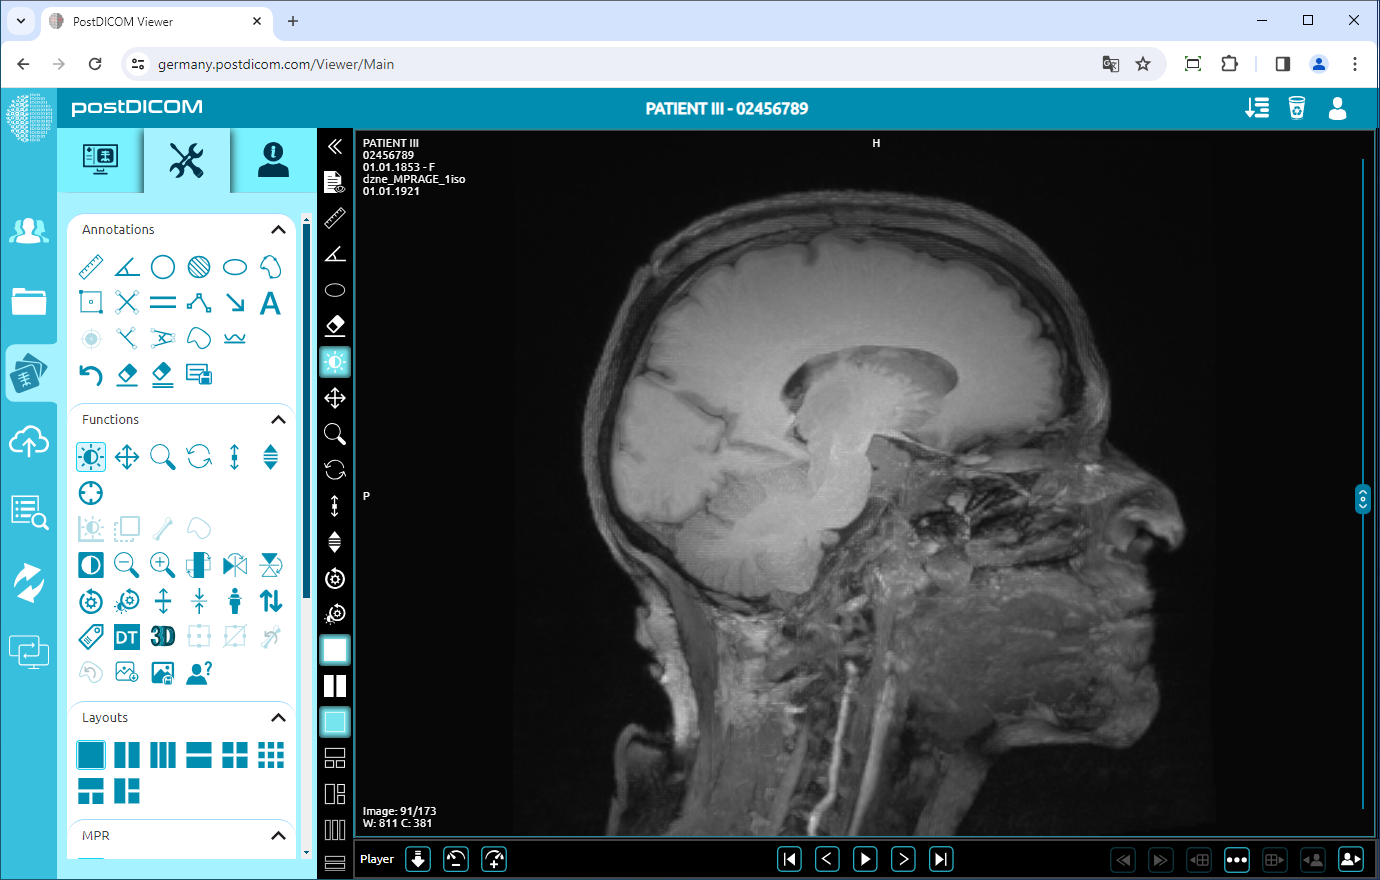

Flip Vertical

Click on the “Flip Vertical” icon on the left side of the page to flip the image vertically.

Once you have clicked, you will see the vertical mirror view of your image on the viewport.